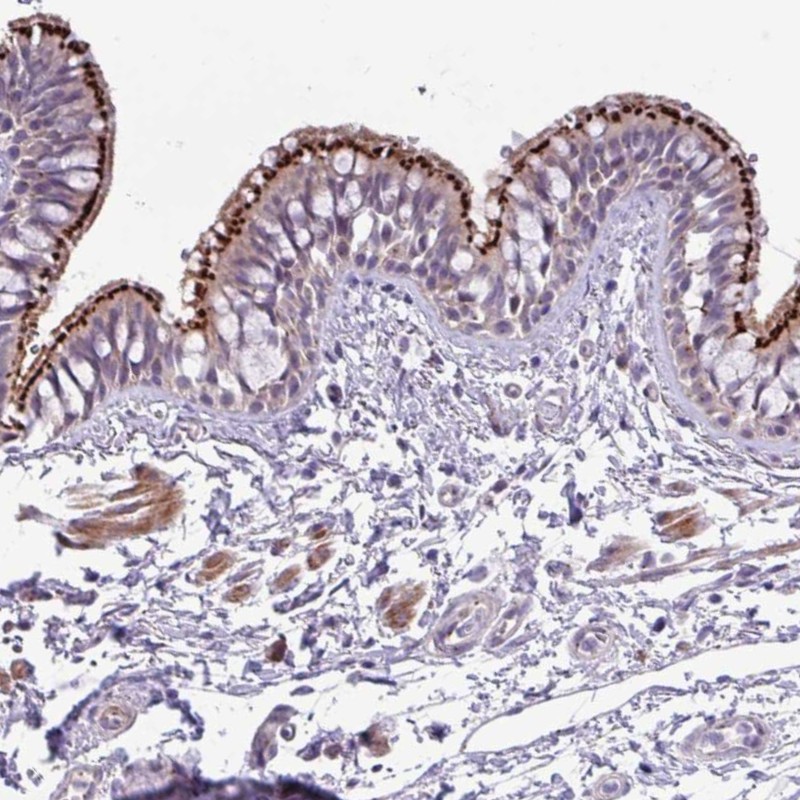

Immunohistochemical staining of human bronchus shows strong dot-like cytoplasmic and membranous positivity in respiratory epithelial cells.